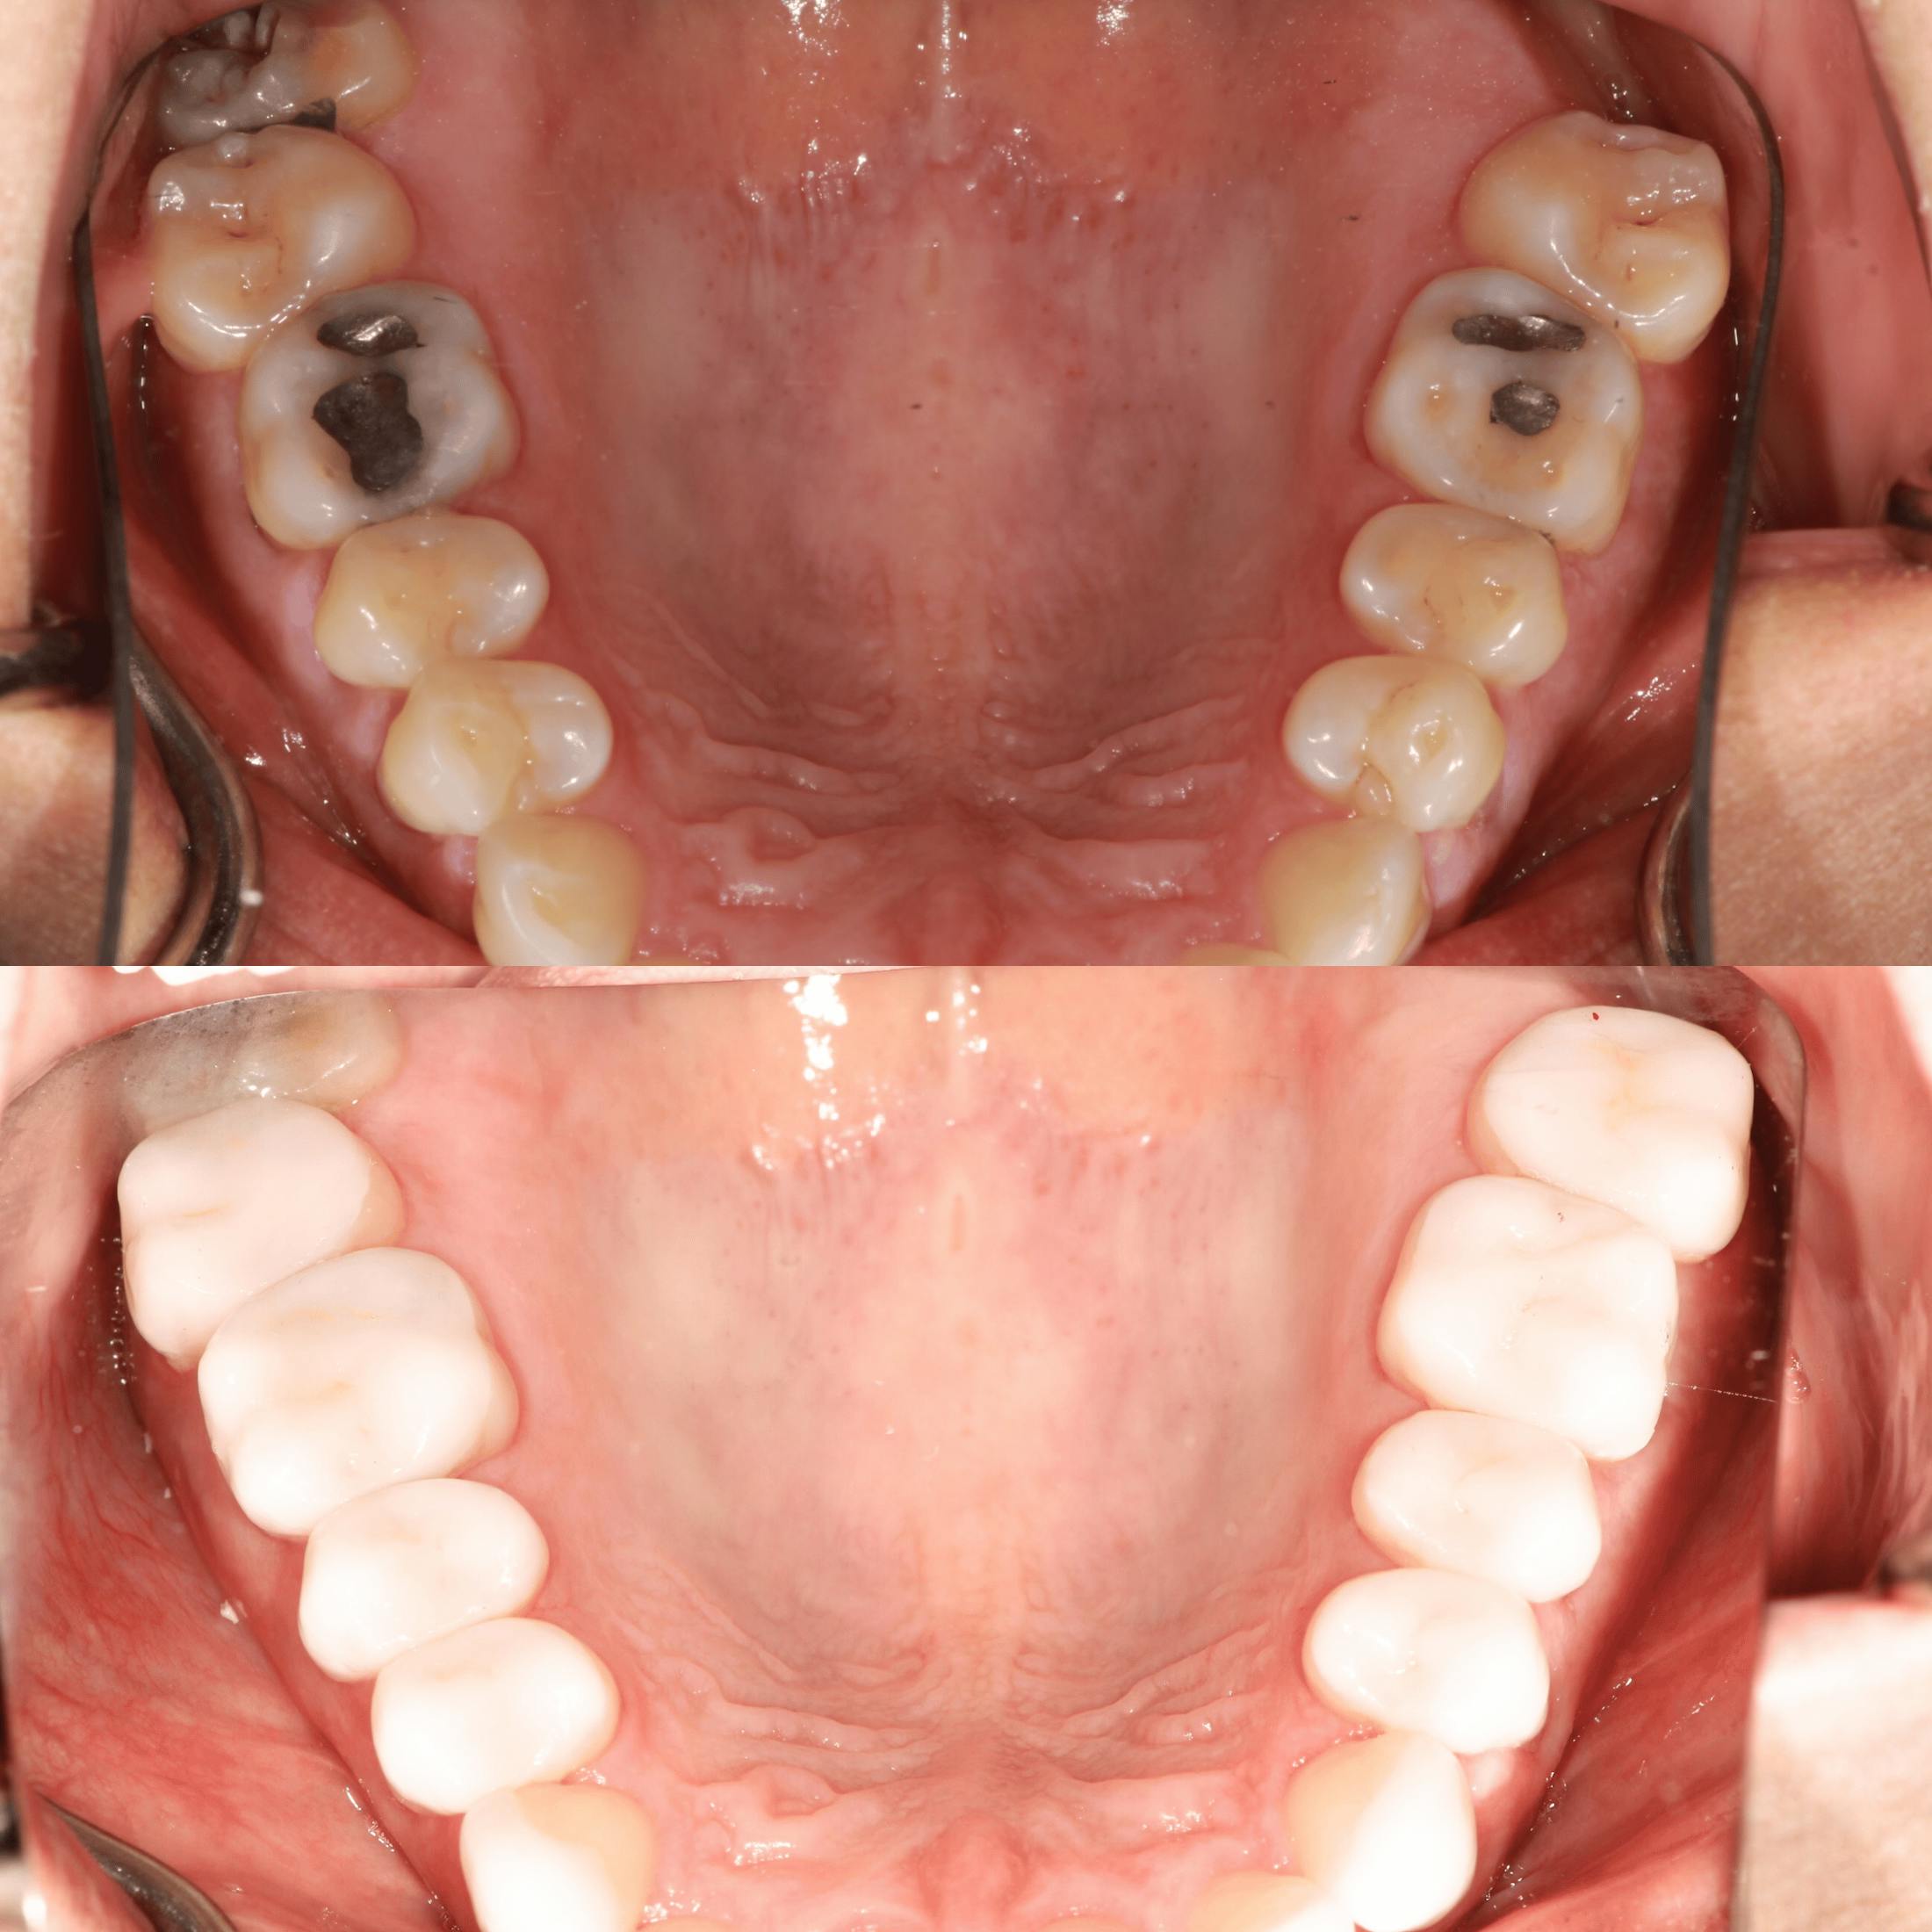

Dr. O’Malley’s holistic care is grounded in the science of biomimetic dentistry: a technique that restores teeth using materials and dental engineering principles to rebuild the teeth as close to mother nature as possible. This process allows him to rebuild strength and flexibility while preserving vitality. Every treatment begins with a comprehensive assessment that considers the relationship between your teeth, bite, gums, and overall wellness. Treatment plans are customized to protect long-term health and reduce the need for future intervention.